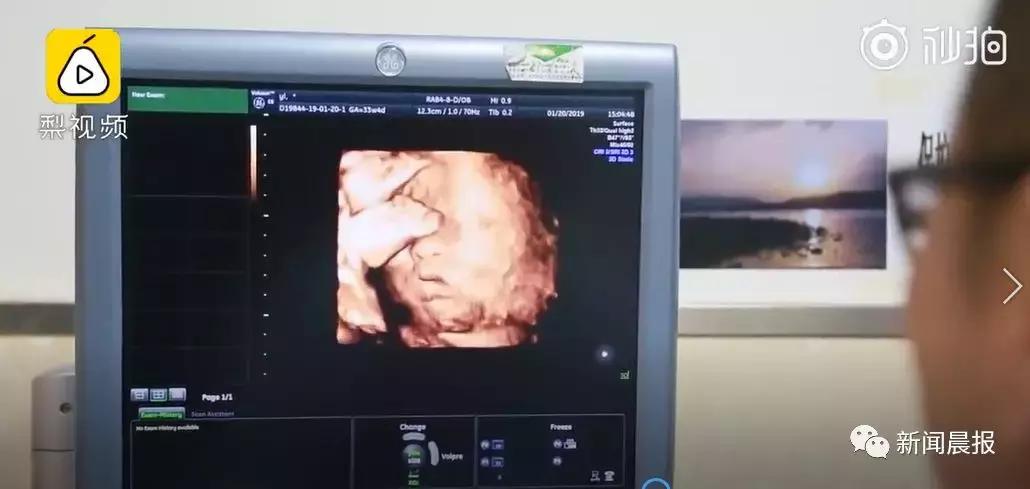

陕西西安一名婴儿

从他外婆的子宫里诞下。

他是中国首个、

全球第十四个

在移植子宫内孕育出生的“添宫宝宝”。

2019年1月20日,历时1小时6分钟的剖宫产手术圆满成功。新出生的宝宝身体指标正常。